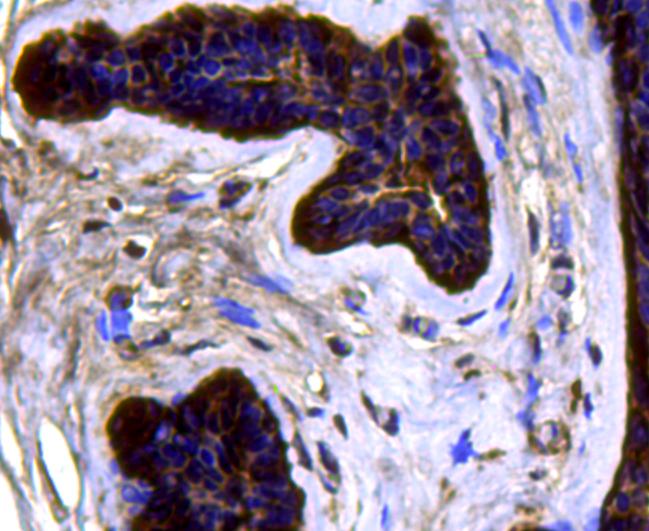

Immunohistochemical analysis of paraffin-embedded human colon cancer tissue using anti-CDK6 antibody. Counter stained with hematoxylin.

Immunohistochemical analysis of paraffin-embedded human breast cancer tissue using anti-CDK6 antibody. Counter stained with hematoxylin.